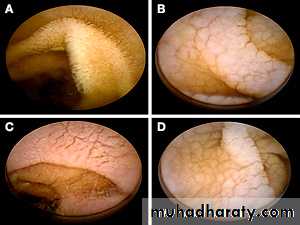

Duodenal biopsy: Endoscopic small bowel biopsy is the gold standard. The histological features are usually characteristic but other causes of villous atrophy should be considered.

-Almost all patients have partial villous atrophy on duodenal biopsy, identical to that seen in coeliac disease, even though they usually have no gastrointestinal symptoms.